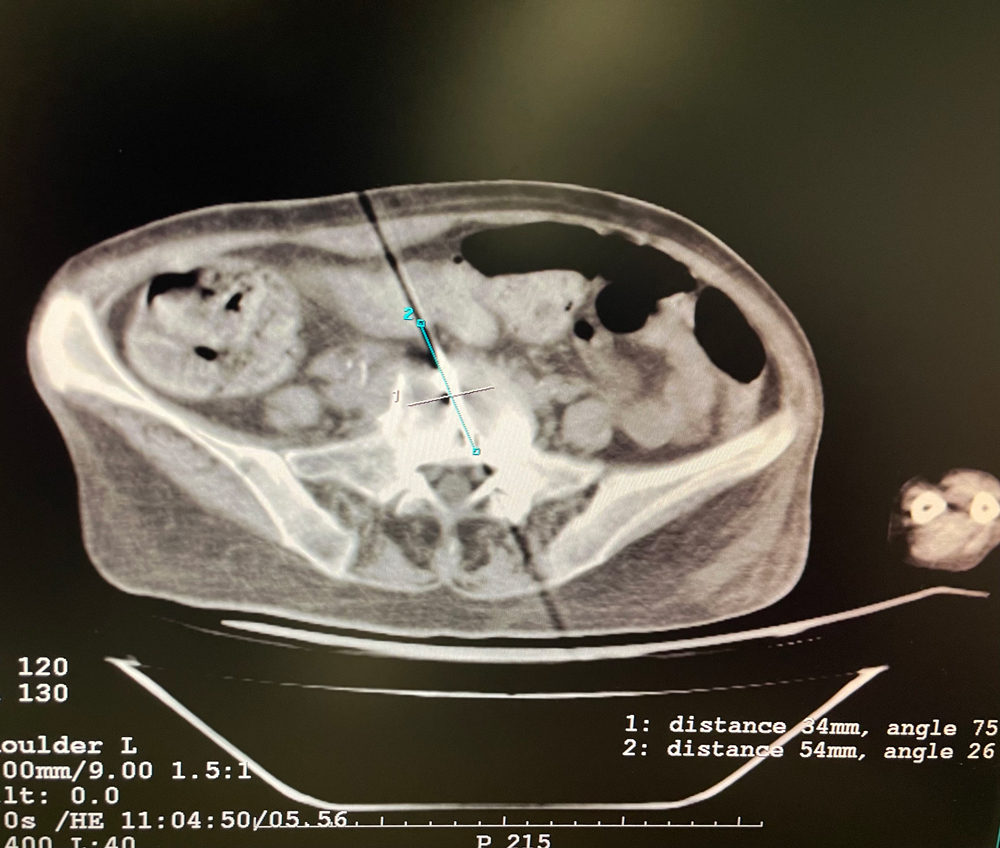

患者一

女,56岁,肺转移瘤,骶骨、左侧肋骨各一转移灶,病灶大小均为5cm。骶骨转移灶、肋骨转移灶各进行2个冻融循环。患者术后状况良好。